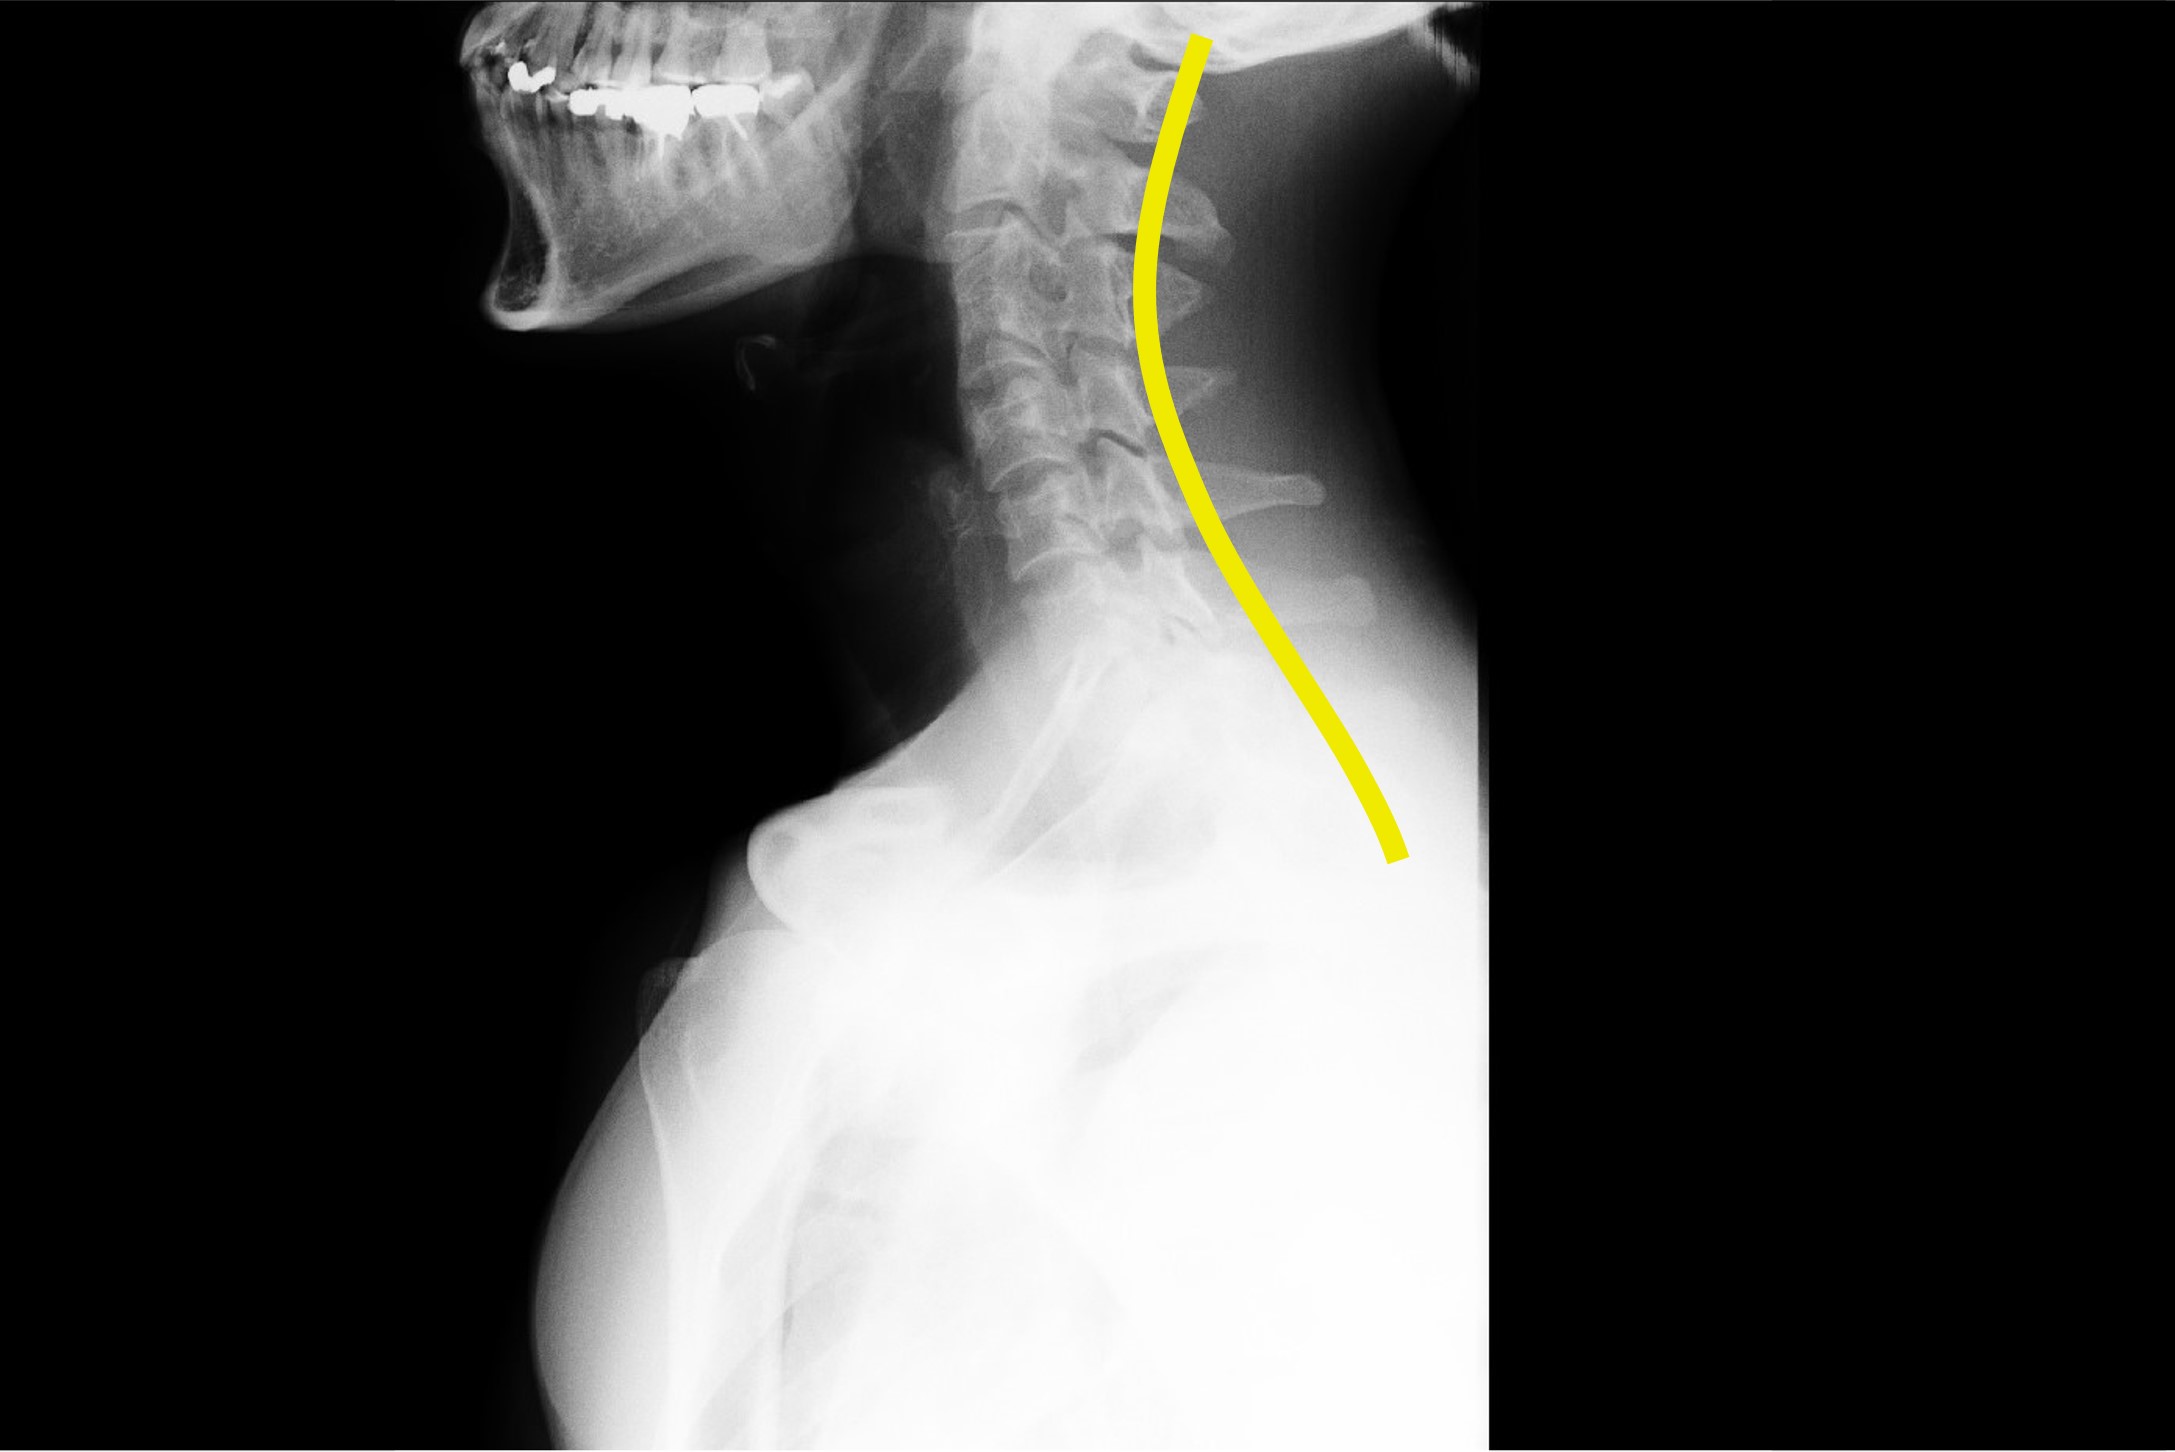

- 姿勢の悪化:猫背や巻き肩が肩こりを悪化させる要因に